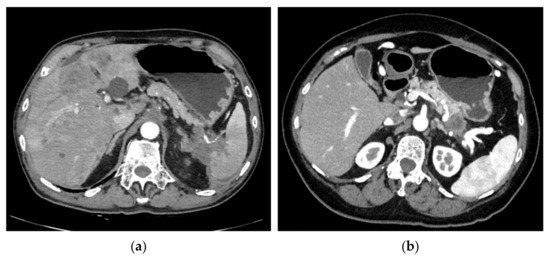

Tumor size was measured along the splenic vein to reflect the degree of splenic vein invasion, which generally, but not always, was also the maximum diameter of the tumor. Vessel invasion was considered present if there was any degree of stenosis in the target vessel, while occlusion was considered present if no contrast passed through the invaded portion of the target vessel. SHI was considered present if the tumor invaded the splenic hilum causing stricture or occlusion where vessels branched out immediately before entering the spleen (Figure 1). Direct contact with, or invasion into, the spleen was therefore not required to meet the definition of SHI. Dilation of the short, posterior, or left gastric veins was defined as a maximum diameter of 5 mm or more at any point along the relevant vein. Splenic index was calculated as largest measurement in the axial plane x largest perpendicular dimension to such measurement x maximum craniocaudal length on coronal reconstruction, and splenomegaly was defined as having a splenic index > 480 [24,25]. The presence of varices was determined based on collateral veins reaching the esophageal or gastric mucosa on contrast-enhanced CT, irrespective of whether varices could be identified on esophagogastroduodenoscopy (EGD). Varices were classified according to Sarin et al.’s classification [26] and were used as a surrogate marker for SPH in this study.

Figure 1. (a) A case with splenic hilar involvement. (b) A case with no splenic hilar involvement.